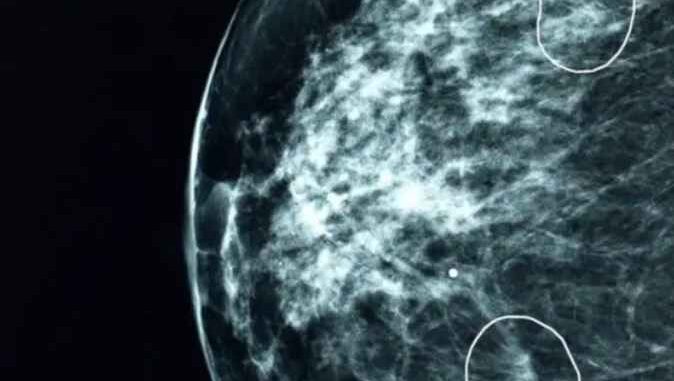

Una herramienta de inteligencia de artificial (IA) que se está probando en el hospitales británicos logró identificar pequeños signos de cáncer de seno en 11 mujeres que habían pasado desapercibidos a la revisión de los médicos.

La herramienta, llamada Mia, se probó en varios centros de salud de Reino Unido y analizó cerca de 10.000 mamografías.

La mayoría de ellas no mostraban signos de cáncer, pero la herramienta logró de manera exitosa identificar las que sí los presentaban, incluyendo las de 11 pacientes que no habían sido diagnosticadas por los médicos.

En sus etapas iniciales, los cánceres pueden ser extremadamente pequeños y difíciles de identificar.

La BBC pudo ver la herramienta en acción en el hospital Grampian, presenciando cómo unos tumores prácticamente invisibles al ojo humano eran señalados por la herramienta.